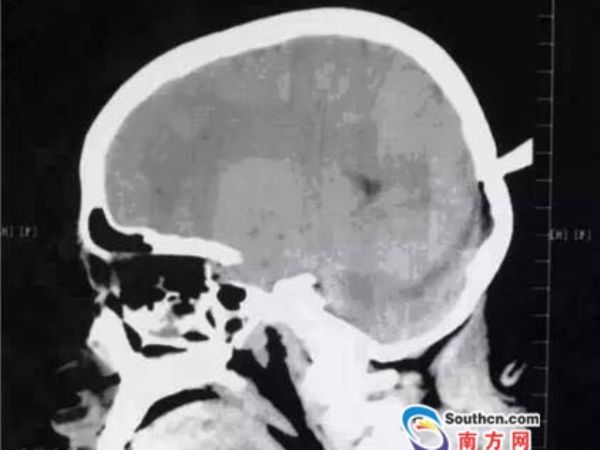

12岁 女孩被飞镖插后脑  穿透颅骨 综合资讯 - 社

女孩被飞镖插后脑 穿透颅骨 生死时速医师跪地